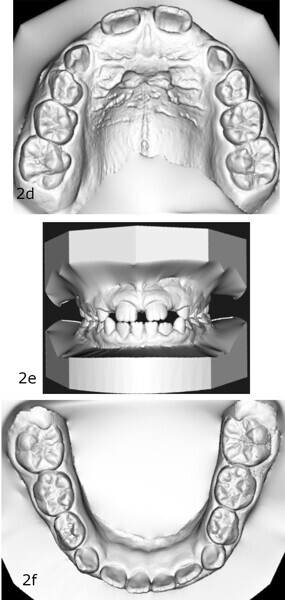

The 8-year-old male patient presented with a diastema between teeth #11 and 21 and non-eruption of teeth #12 and 22 (Fig. 1). The patient underwent a thorough orthodontic examination, including intra-oral photographs, extra-oral photographs, cephalometric radiography of the skull with cephalometric tracing, dental panoramic tomograms, impressions by intra-oral scanning, and functional and phonetic tests. Intra-oral examination (Fig. 2) and pattern analysis showed a Class I molar and canine relationship and contraction of the maxillary arch, displaced pre-contact between teeth #63 and 73, a 3.7 mm diastema between teeth #11 and 21, a mandibular midline deviation to the left, a maxillary midline to the right, and an open bite (−1.5 mm).

After 18 months of therapy, a case reassessment was carried out to verify that the goals had all been achieved (Fig. 8). Comparison of extra-oral photographs at the start of treatment (T0) and end of treatment (T1; Fig. 9) showed that excellent balance of the patient’s face had been achieved with a regular, symmetrical smile. Comparison of the intra-oral photographs (Fig. 10) and models (Fig. 11) also showed wider and more harmonious arch forms, closure of the anterior diastema, closure of the open bite and recentring of the mandibular midline. Excellent gingival trophism had also appeared.

Analysis of the models in Autodesk Netfabb software (Fig. 12) showed regularisation of the arches and an increase in the maxillary inter-canine diameter of 2.61 mm and in the maxillary intermolar diameter of 2.29 mm. The superimposition of the arches at T0 and T1 (Fig. 13), performed using OnyxCeph3 (Image Instruments), was very significant and showed the shift from the initial arch shape and size to a wider shape posteriorly but with significant control of the maxillary incisor area.